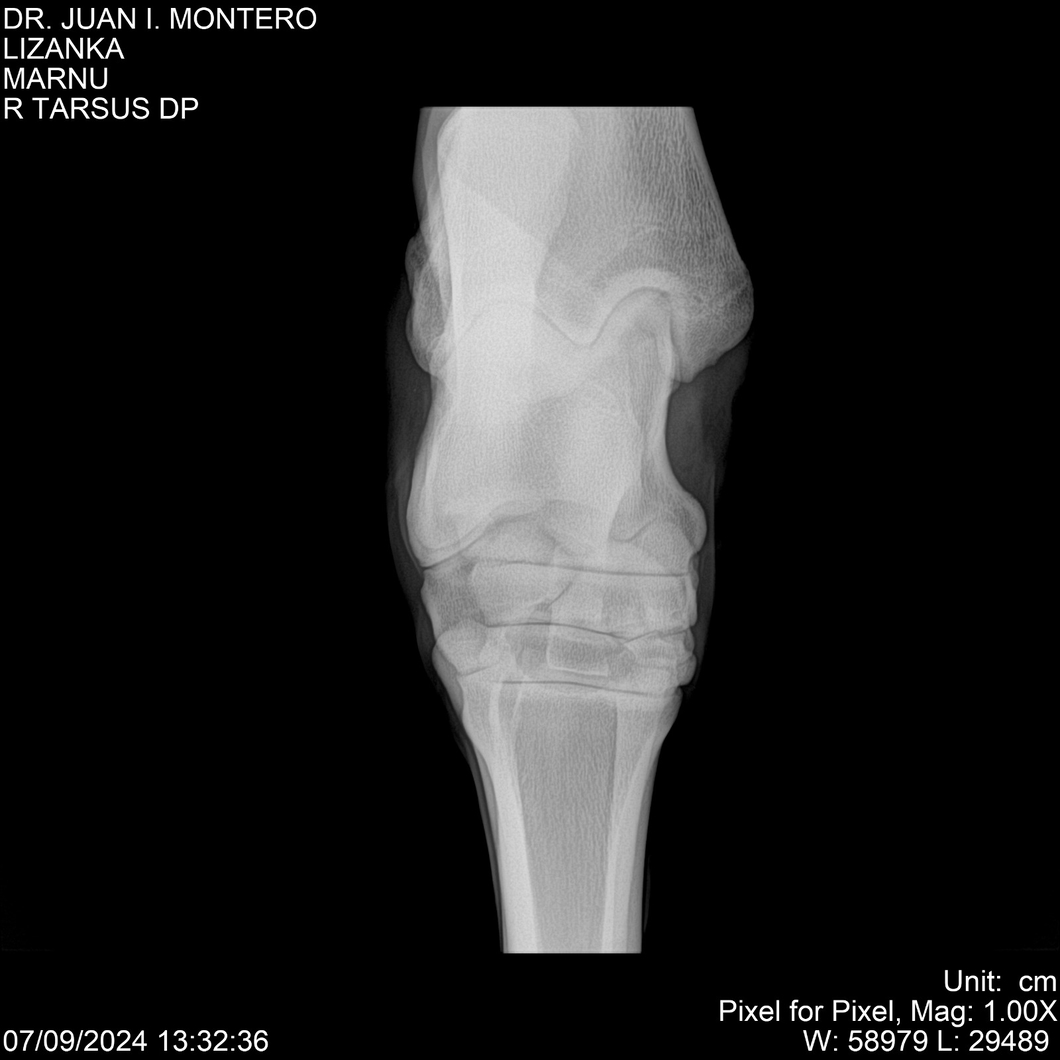

LOTE 18, LIZANKA Lote Anterior Volver al remate Lote Siguiente Ficha Contacto Montevideo - Ficha del Lote Identificador: #282512 Categoría: Yeguarizos Montevideo - 62 Visualizaciones ClicData Contacto Empresa: Abelenda N. R., Walter Hugo Nombre*: Teléfono* : E-mail* : Mensaje Enviar Registrese gratis Este contenido Exclusivo está disponible sólo para usuarios registrados Ingresar